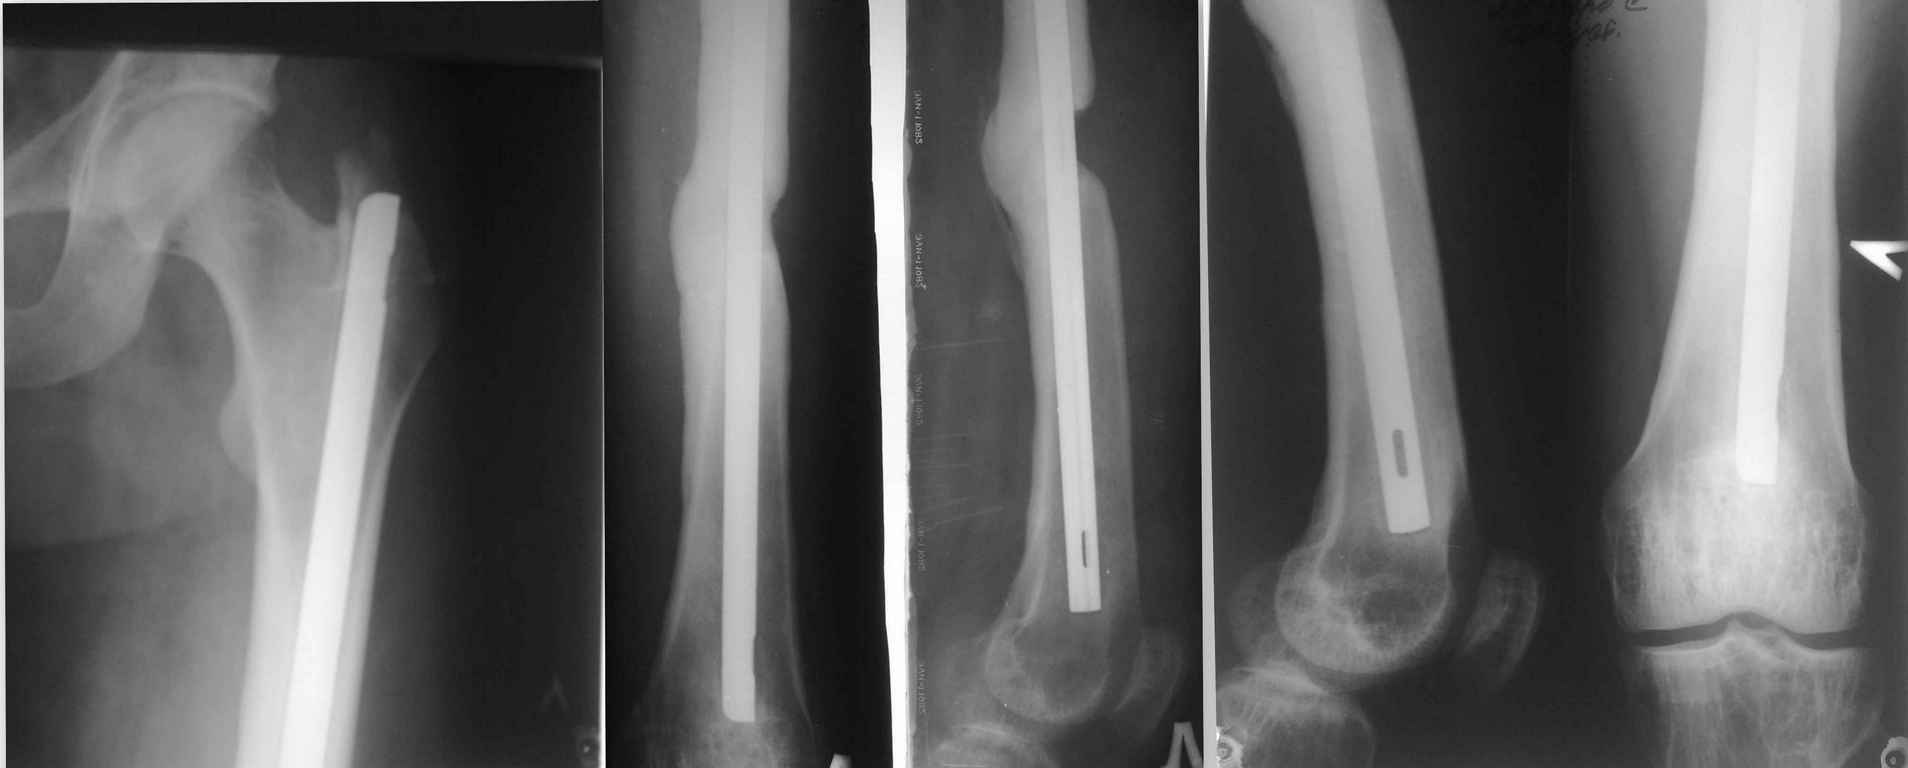

Здравствуйте Уважаемые коллеги! Просим совета. Есть больной 35 лет. Который получил сочетанную травму в результате ДТП более 2х лет назад. Оперирован на бедре МОС бедра штифтом, на голени накостной пластиной, которая через 2-3 мес. осложнилась развитием остеомиелита, попал затем к нам. Мы удалили пластину с Б/б кости и фиксировали в ВЧКО. Длительно лечился у нас с остеомиелитом б/б кости левой голени и по месту жительства, в общем, с голенью вроде всё в порядке на данный момент свищей нет. Бедро, сделанное в местной больнице ранее, тоже не беспокоило, но теперь начало, по снимкам бедра, сделанным ранее около года назад отмечается миграция стержня в бедре до 1.5 см. и появился на снимке дефект кости в области перелома. Ранее его не было. Кожных трофических нарушений нет. Металл не пальпируется. Больной настаивает на удаление металла. Как быть с учётом дефекта кости: удалять полностью штифт, с костной аутопластикой? БИОС?

беспокоило, но теперь начало, по снимкам бедра, сделанным ранее около года назад отмечается

миграция стержня в бедре до 1.5 см.

А куда миграция? Что-то непохоже. Можно через годик снимок сделать еще.

и появился на снимке дефект кости в области перелома. Ранее

его не было.

Этот дефект явно был, даже видно компенсаторное утолщение спайки с другой стороны.

Наверно, снимок в этой проекции наконец-то сделали.

В общем, пока не видно никаких проблем, которые удаление стержня решит.

Не очень понятно: беспокоят-то больного снимки, или все-таки клиника есть? Если снимки - попробуйте убедить больного, что "мозоль несимметричная, механически слабая, после удаления может произойти повторный перелом и т.п". Ну сделайте, в конце концов свежие снимки, сравните.Миграции действительно не заметно.

Всем добрый вечер! Судя по закругленным краям кости, диастаз был всегда, может из-за остеомиелита было не до него. Если беспокоит больного, то что? если нет клиники, к сожалению наверное чуда не будет, "красивее" сама костная мозоль не станет, т.к. в дефекте между костями красуется гвоздь и рубцовые ткани. пусть живет, если у больного нет удлинения конечности.

Снимки эти последние! Ранее делались около года назад. Укорочение или удлинение конечности нет. Клиники нет! Просто хочет попрощаться со штифтом, даже настаивает. Просто если сравнивать их и новые есть небольшая миграция стержня дистально до 1,5 см не более! Снимки для сравнения сброшу. Спасибо за советы.

Добрый день! В самом деле, костная мозоль асимметричная, механическая прочность ее на изгиб наверняка неидеальна. Но, даже не вдаваясь в тонкости прочностных характеристик костной мозоли, в "красках" опишите пациенту технику удаления стержня в ТАКОЙ ситуации - трепанация кости (скорее всего - на большом протяжении), вероятность заклинивания штифта "насмерть" при выходе на 10-15 см над вертелом с последующим непредсказуемым отпиливанием-откусыванием и т.д. и т.п. - одумается! Удачи!

Прооперировали нашего пациента!Не одумался!Сделали ревизию верхнего конца штифта:Штифт подвижный легко удаляется,произвели ревизию место перелома с аутопластикой губкой. Заблокировали верхний конец штифта винтом.Послеоперационный период через 14 дней осложнился открытием свища на голени. Лечим!